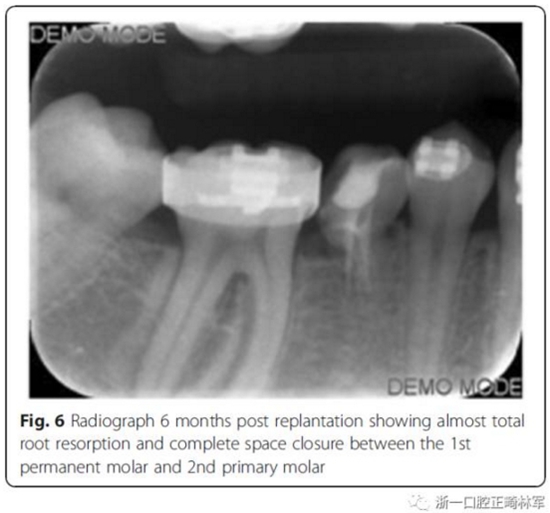

第6個(gè)月,臨床和影像檢查顯示乳牙幾近完全的替代性牙根吸收和間隙的完全關(guān)閉。最終,將乳磨牙拔除并開(kāi)始進(jìn)行完整的正畸治療。在接下來(lái)一年,用0.017’’*0.025’’末端回彎的不銹鋼弓絲和彈性牽引剩余間隙關(guān)閉,并以II類(lèi)牽引作為支持。